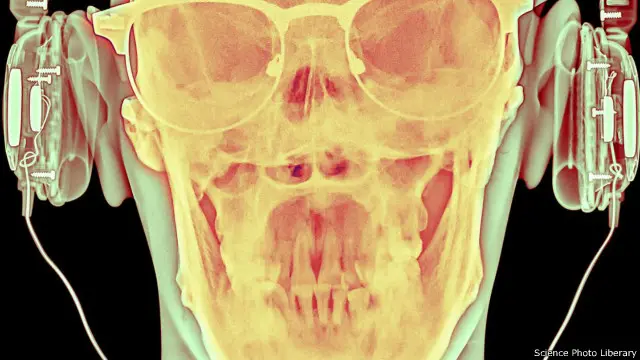

هل ندمر قدرتنا على السمع دون أن ندري؟

يستخدم كثيرون سماعات الأذن على مدار ساعات اليوم لحجب الضوضاء عن مسامعنا سواء خلال تنقلاتنا أو أثناء وجودنا في مكان العمل. لكن هل يؤدي ذلك إلى تدمير قدرتنا على السمع مبكرا؟ في السطور التالية؛ تتحرى مولي كراين صحة هذه الفرضية.

ويعتقد بعض الخبراء أن بعض السلوكيات المرتبطة بالأنماط الحديثة للغاية للحياة – مثل استخدامنا المتزايد لسماعات الأذن للاستماع للموسيقى وحوارات الأفلام – ربما يسهم في تدمير قدرتنا على السمع. وقد تؤثر هذه المشكلة على البالغين ممن لا يزالون في مقتبل العمر، وذلك بشكل أكبر بكثير مما كان الحال عليه من قبل.